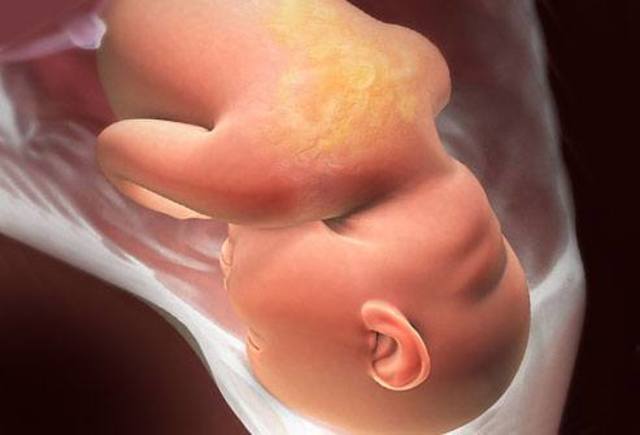

Mantiene una postura que le permite ocupar menos espacio: la cabeza hacia abajo, los brazos cruzados sobre el pecho, las piernas elevadas y dobladas. Es lo que se conoce como postura fetal.

Ahora el bebé pesa alrededor de 3 o 3,5 kilos y su longitud oscila entre los 49 y los 53 centímetros. Tiene unas uñas muy largas.